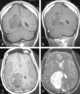

Minimally enhancing intracranial lesion

A traumatic brain injury (TBI), also known as an intracranial injury, is an injury to the brain caused by an external force. TBI can be classified based on severity (ranging from mild traumatic brain injury [mTBI/concussion] to severe traumatic brain injury), mechanism (closed or penetrating head injury), or other features (e.g., occurring in a specific location or over a widespread area). [Source: Wikipedia ]